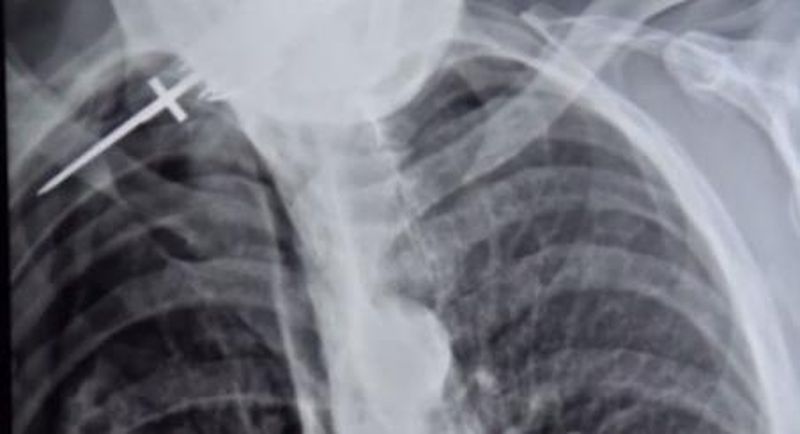

O femeie de 45 de ani, din satul sucevean Clit, a fost arestata pentru 30 de zile, pentru ca si-a injunghiat concubinul.

Incidentul a avut loc pe 11 iunie, cand femeia a sunat la 112 si a anuntat ca iubitul ei a fost injunghiat cu un cutit in spate, de un allt barbat. Varianta femeii a fost sustinuta si de victima, spunand ca nu a recunoscut persoana care l-a injunghiat.

In urma verificarilor facute de politisti s-a constatat ca barbatul a fost injunghiat de iubita lui, in urma unui conflict, dupa ce au amandoi au consumat bauturi alcoolice, noteaza suceavanews.ro.